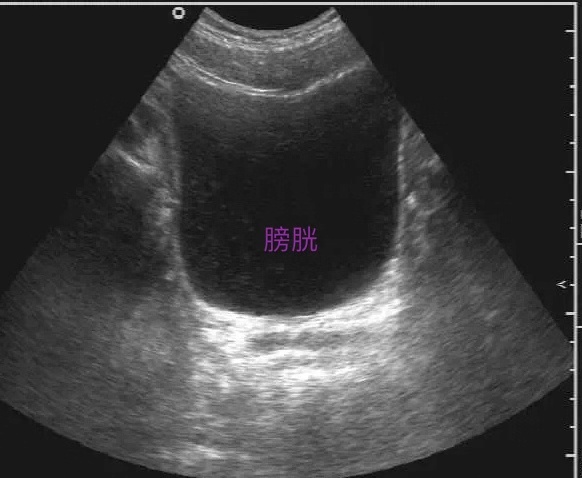

1. 膀胱

检查膀胱需要憋尿憋的刚刚好,才能更好观察膀胱壁的轮廓、连续性和完整性,厚度,内壁有无凹陷和隆起,有无占位性病变及其浸润程度。但不能过度,过度了也会产生假像。一般情况以喝完1000ml温开水后半小时检查为宜